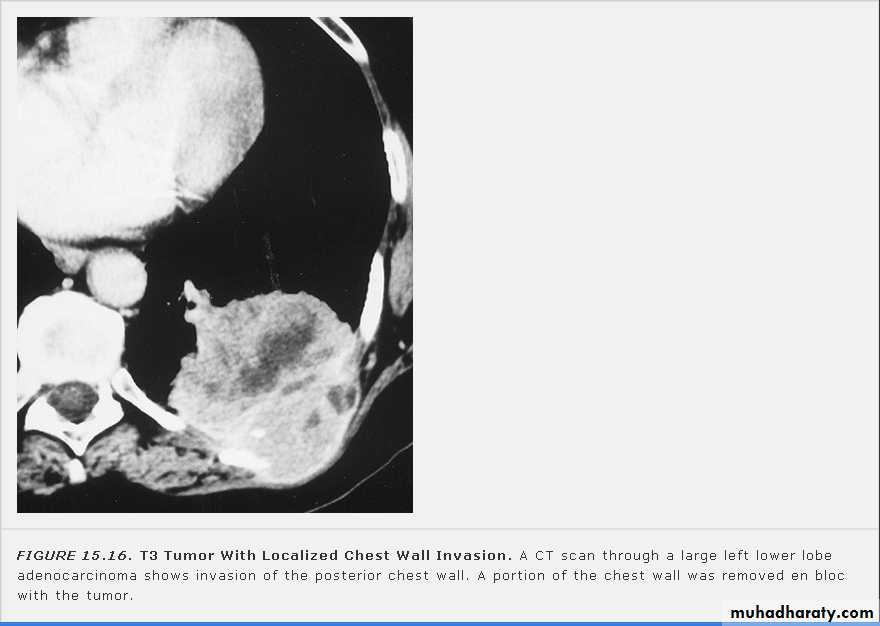

Nodular (coin) lesion in the left upper lung with irregular edge (most probably cancinoma